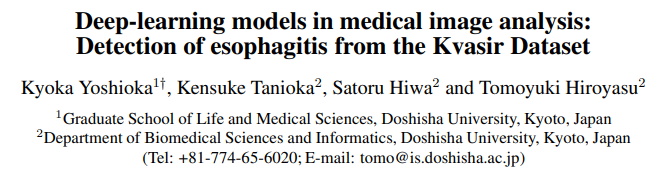

▌Deep-learning models in medical image analysis: Detection of esophagitis from the Kvasir Dataset

作者单位:同志社大学(日本)

论文链接:https://arxiv.org/abs/2301.02390

本研究旨在比较卷积神经网络模型(GoogLeNet、ResNet-50、MobileNet V2和MobileNet V3)在开放的Kvasir数据集的内窥镜图像中检测食管炎的准确性。结果显示,在这些模型中,GoogLeNet取得了最高的F1分数。根据真实阳性率的平均值,MobileNet V3比其他模型更有把握地预测食管炎。